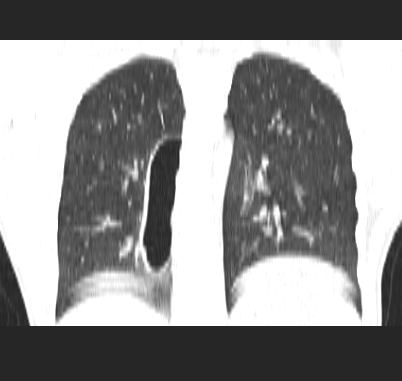

标题: CT19170:男 24岁,胸部外伤一周行CT检查 [打印本页]

男 24岁,胸部外伤一周行ct检查 未传纵隔窗

首先考虑肺裂伤形成的液气囊肿.纵膈胸膜包裹性的液气胸可能性小,病变主要在肺内.